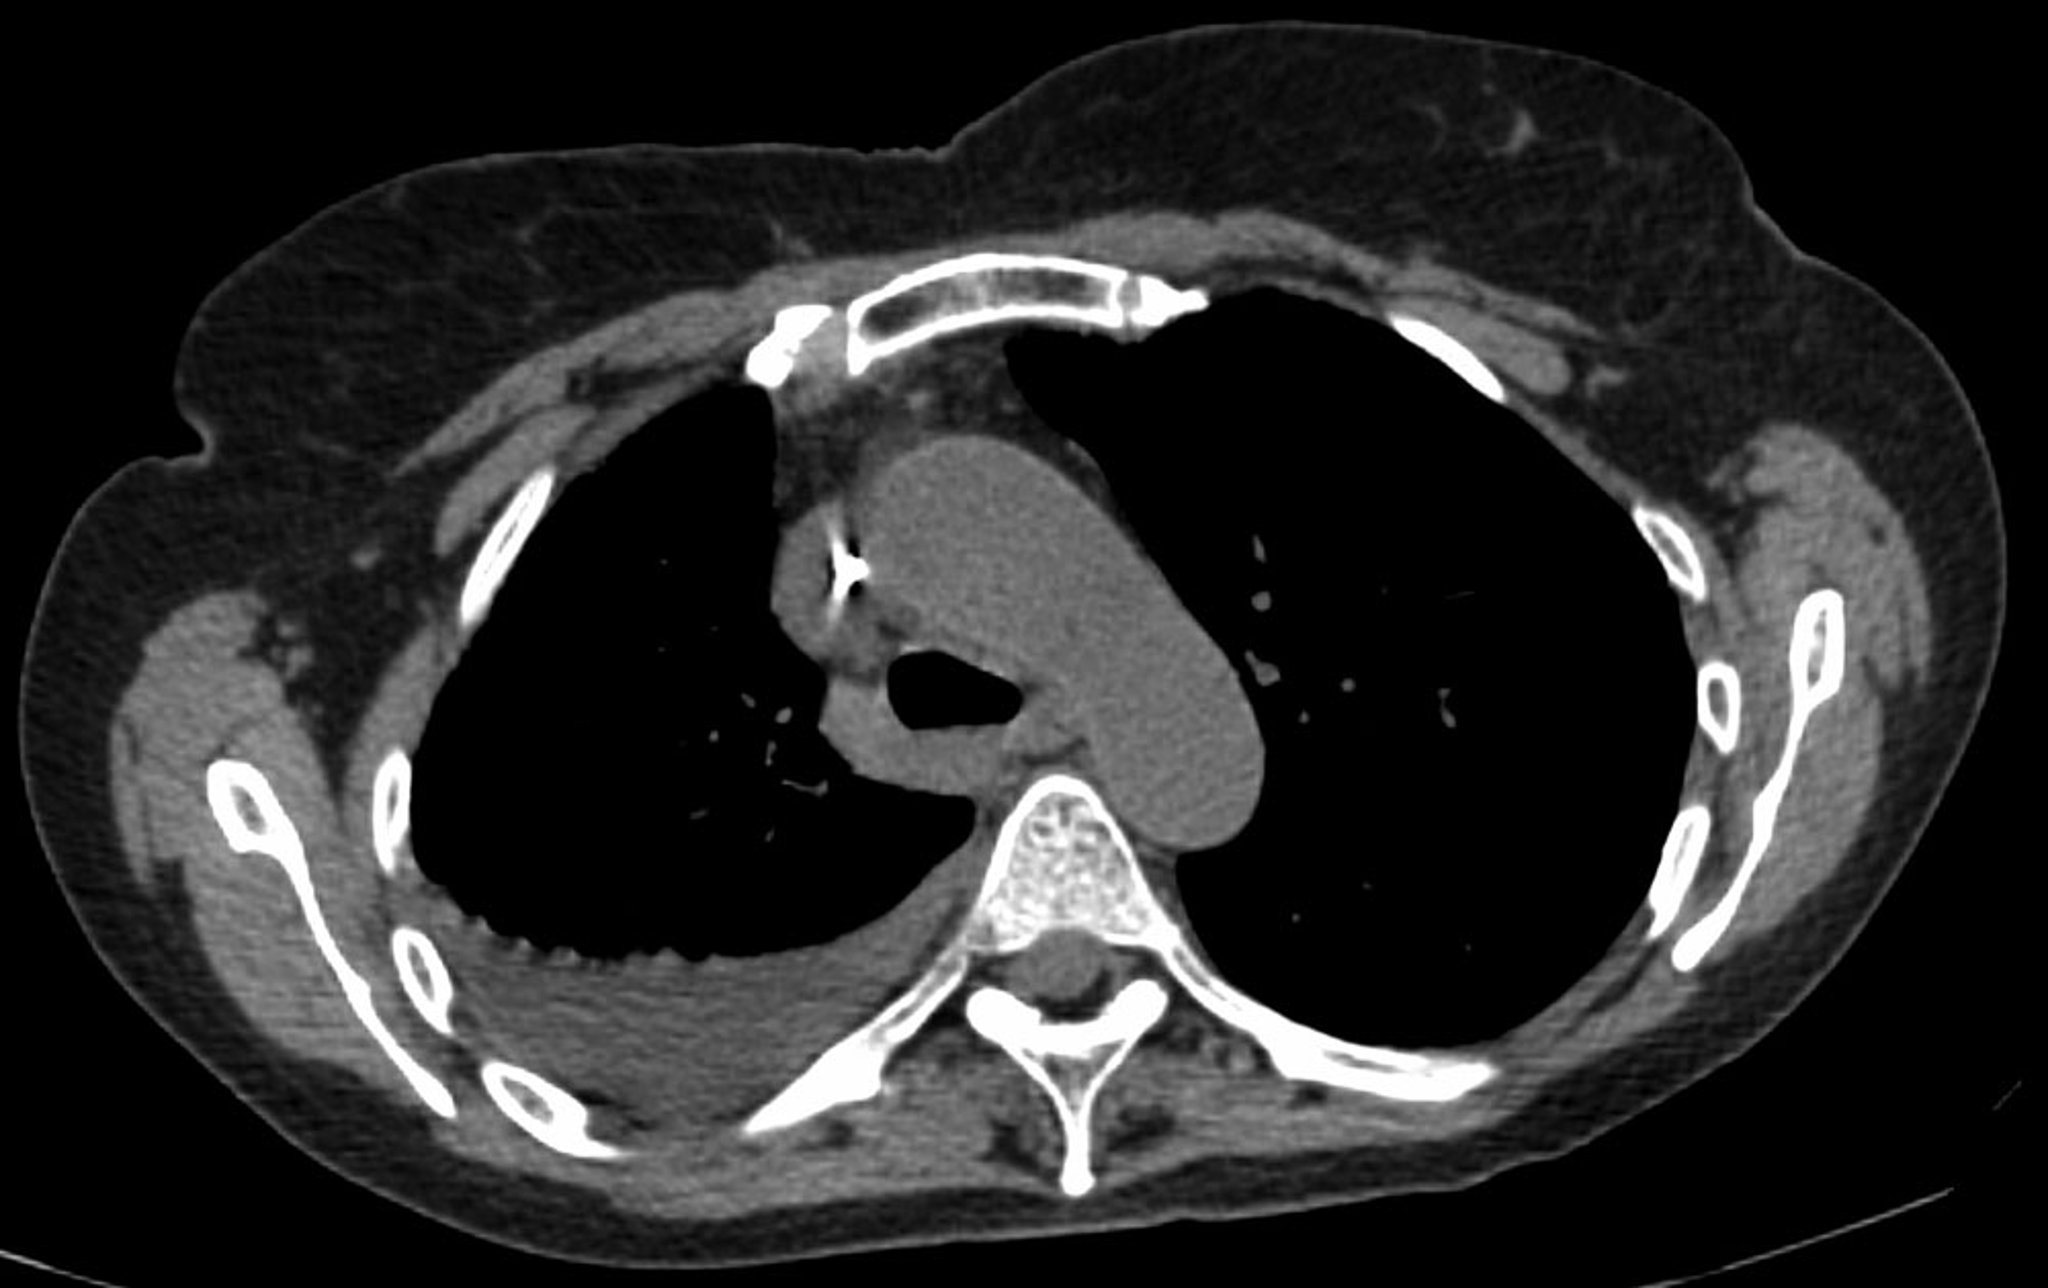

La radiografía de tórax es la primera prueba que se realiza para confirmar la presencia de líquido pleural. Debe examinarse la radiografía lateral del tórax en posición de pie cuando se sospecha un derrame pleural. En esa posición, 75 mL de líquido producen el borramiento del ángulo costofrénico posterior. El borramiento del ángulo costofrénico lateral suele necesitar cerca de 175 mL, pero puede requerir hasta 500 mL. Las radiografías en decúbito lateral (con el lado del derrame hacia abajo) pueden detectar pequeños volúmenes de líquido más fácilmente que las radiografías estándar en posición vertical, particularmente con un derrame de flujo libre. Los derrames pleurales más grandes opacifican porciones del hemitórax y pueden provocar desplazamiento mediastínico; los derrames > 4 L pueden causar opacificación completa del hemitórax y desplazamiento mediastínico hacia el lado contralateral.

Los derrames tabicados son colecciones de líquido atrapado por adherencias pleurales o dentro de las cisuras pulmonares. Estudios por imágenes adicionales (radiografías de tórax en decúbito lateral, la TC o la ecografía) deben realizarse si no está claro si una densidad radiográfica representa líquido o Infiltrados parenquimatosos o si el líquido sospechoso es tabicado o fluye libremente; estas pruebas son más sensibles que las radiografías de pie y pueden detectar pequeños volúmenes líquidos. Los derrames tabicados, en particular los de la cisura oblicua u horizontal, pueden ser confundidos con una masa pulmonar sólida (seudotumor). Pueden cambiar de forma y tamaño con los cambios de posición del paciente y la cantidad de líquido pleural.

La ecografía torácica se considera una prueba de referencia para el diagnóstico del derrame pleural y es realizada e interpretada por médicos junto a la cama del paciente. Es muy precisa para la detección de pequeños volúmenes de líquido pleural y proporciona información diagnóstica adicional (p. ej., la presencia de tabique, engrosamiento pleural).

La TC con contraste venoso es la siguiente prueba, muy útil para proporcionar información sobre el realce pleural y la posible nodularidad pleural. (La TC sin contraste puede usarse para la evaluación inicial pero no puede excluir una neoplasia maligna o una infección). La TC con contraste venoso es valiosa para evaluar el parénquima pulmonar subyacente en cuanto a la presencia de infiltrados o masas cuando el pulmón está oculto por el derrame o cuando el detalle en las radiografías de tórax es insuficiente para distinguir el líquido tabicado de una masa sólida.